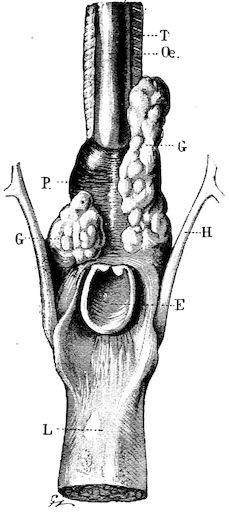

| Tumours of the larynx | 335 | |||

| Physiological anomalies | 567 | |||